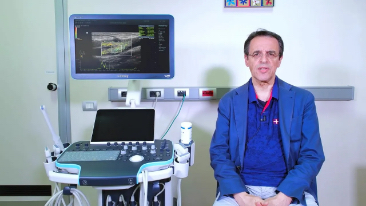

Resona 7

Gelombang Baru dalam Inovasi Ultrasound

Sejak didirikan, Mindray terus mencari cara baru untuk meningkatkan keandalan diagnostik. Didukung Teknologi ZONE Sonography? terkini, platform ZST+ baru Resona 7 meningkatkan kualitas gambar ultrasound melalui pengambilan zona dan pemrosesan data saluran.

Selain kualitas gambar premium, Resona 7 juga meningkatkan kemampuan penelitian klinis dengan V Flow revolusioner untuk evaluasi hemodinamika vaskular, serta pengambilan penampang tercanggih dari rangkaian data 3D untuk diagnosis CNS pada janin. Kombinasi pengoperasian multisentuh berbasis gerakan yang paling intuitif dengan semua fitur klinis penting membuat Resona 7 menjadi gebrakan baru dalam inovasi ultrasound.